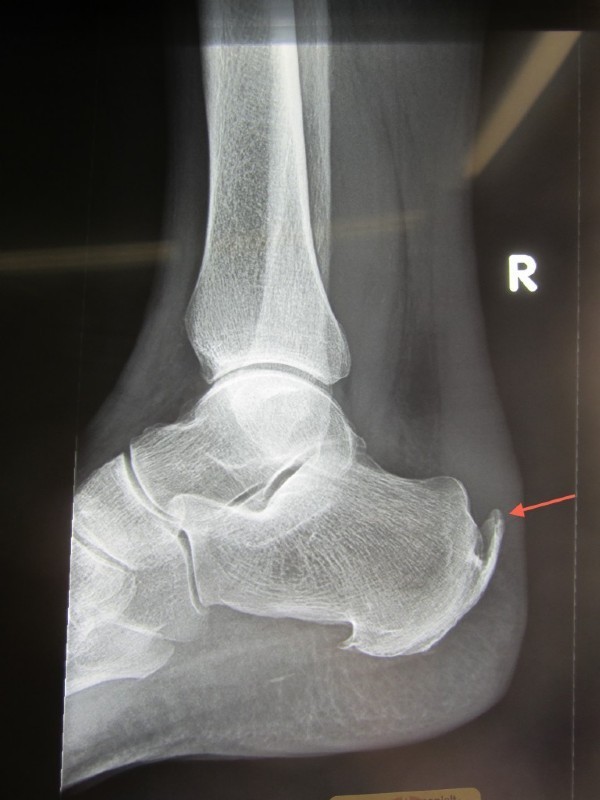

Bild 2: Im Röntgen zeigt sich neben dem hohen Fersenbein aber ein großer oberer Fersensporn, der vermuten lässt, dass die Achillessehne zumindest einen Teilriss aufweist.